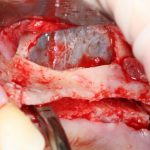

Вот клиническая картина через 4 месяца после ранее проведенной имплантации с остеопластикой:

Как видишь, коллеги из недалекой дружественной страны не осилили снятие швов. Мне это не нравится, хотя и объясняет, почему люди готовы ехать за тыщи километров ради 20-минутной операции удаления зуба мудрости.

Ну хорошо. Швы сняли. Делаем разрез. Обрати внимание, что после всех проведенных операций у нас остается очень небольшой по ширине слой жевательной слизистой оболочки: